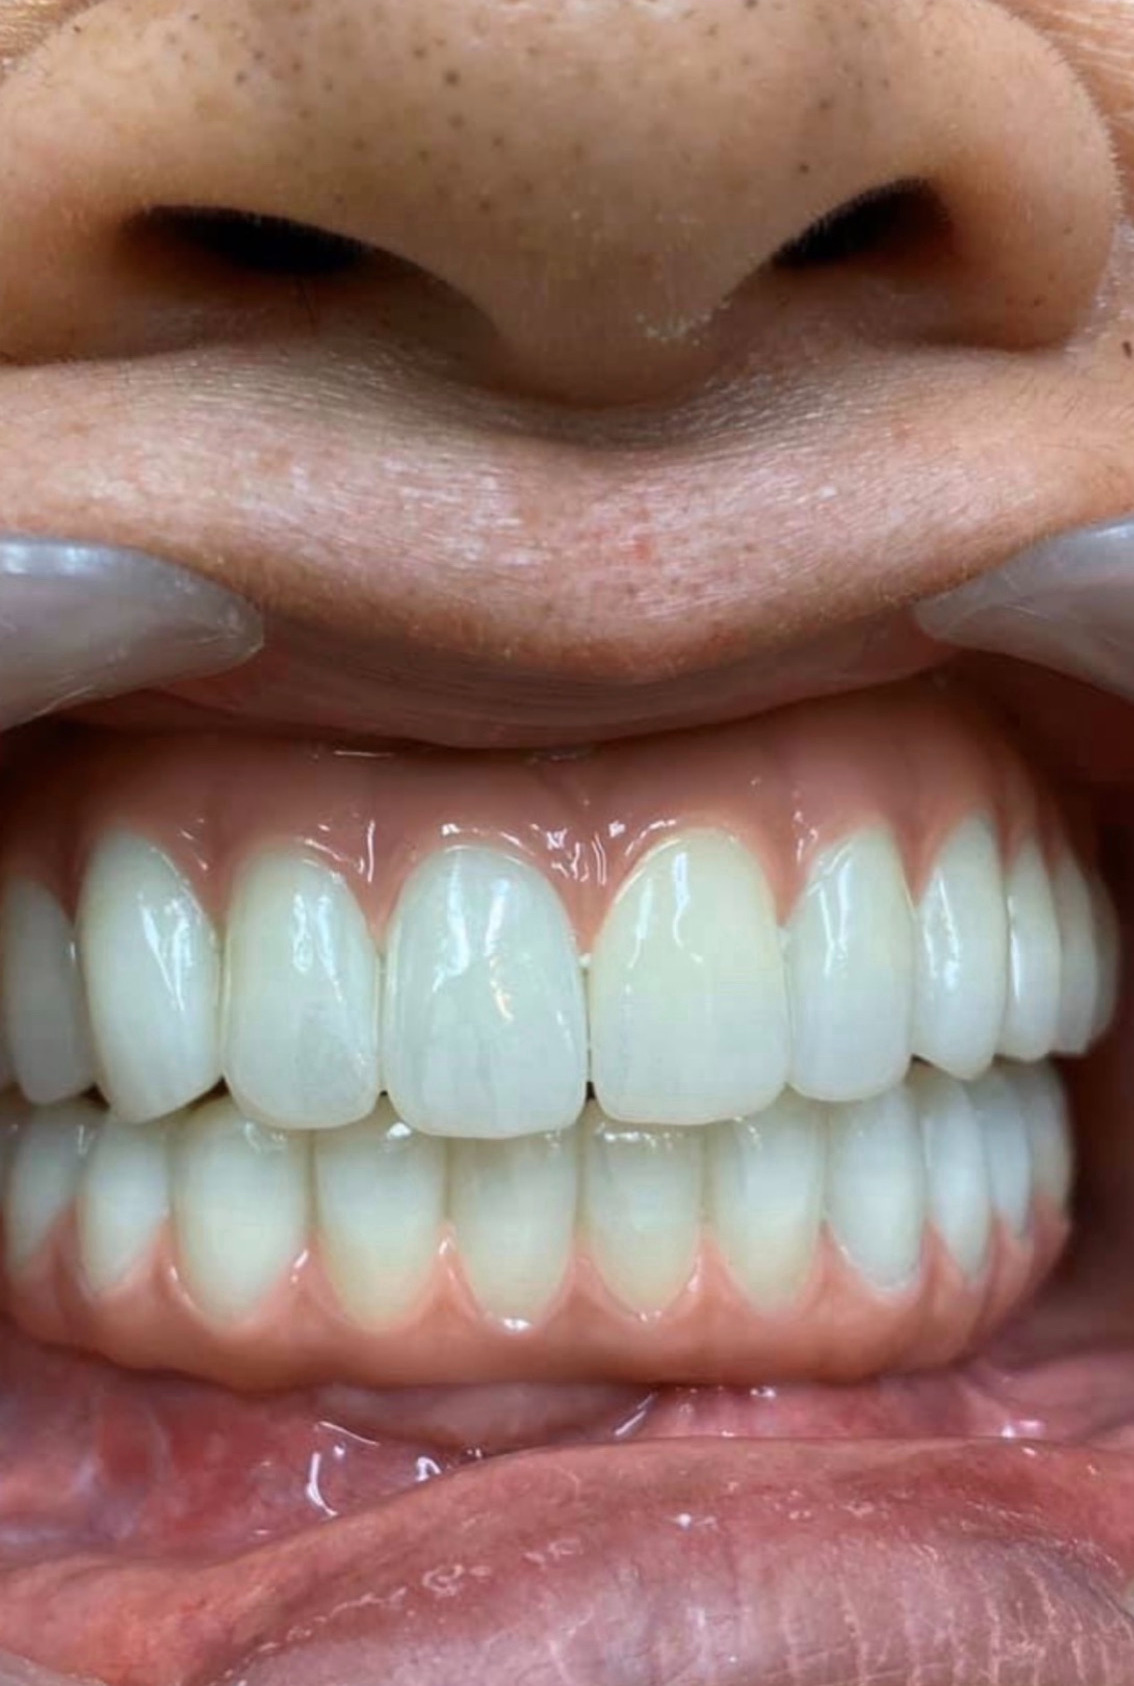

オールオン4の症例

All-on-4芝公園は日本国内でも有数のAll-on-4の治療実績を誇っております。

All-on-4芝公園にてAll-on-4の処置を実施した実際の症例です。似たような症状でお悩みの方は一度ご相談ください。

この患者様は上顎、下顎ともAll-on-4を同時に一日で行いました。

手術の前に残っていた歯はグラグラしていた為、手術当日に抜歯。すぐにインプラントを埋入しました。骨が安定するまで3ヶ月ほど仮歯で過ごしていただき、その後セラミックスのきれいな歯を装着します。